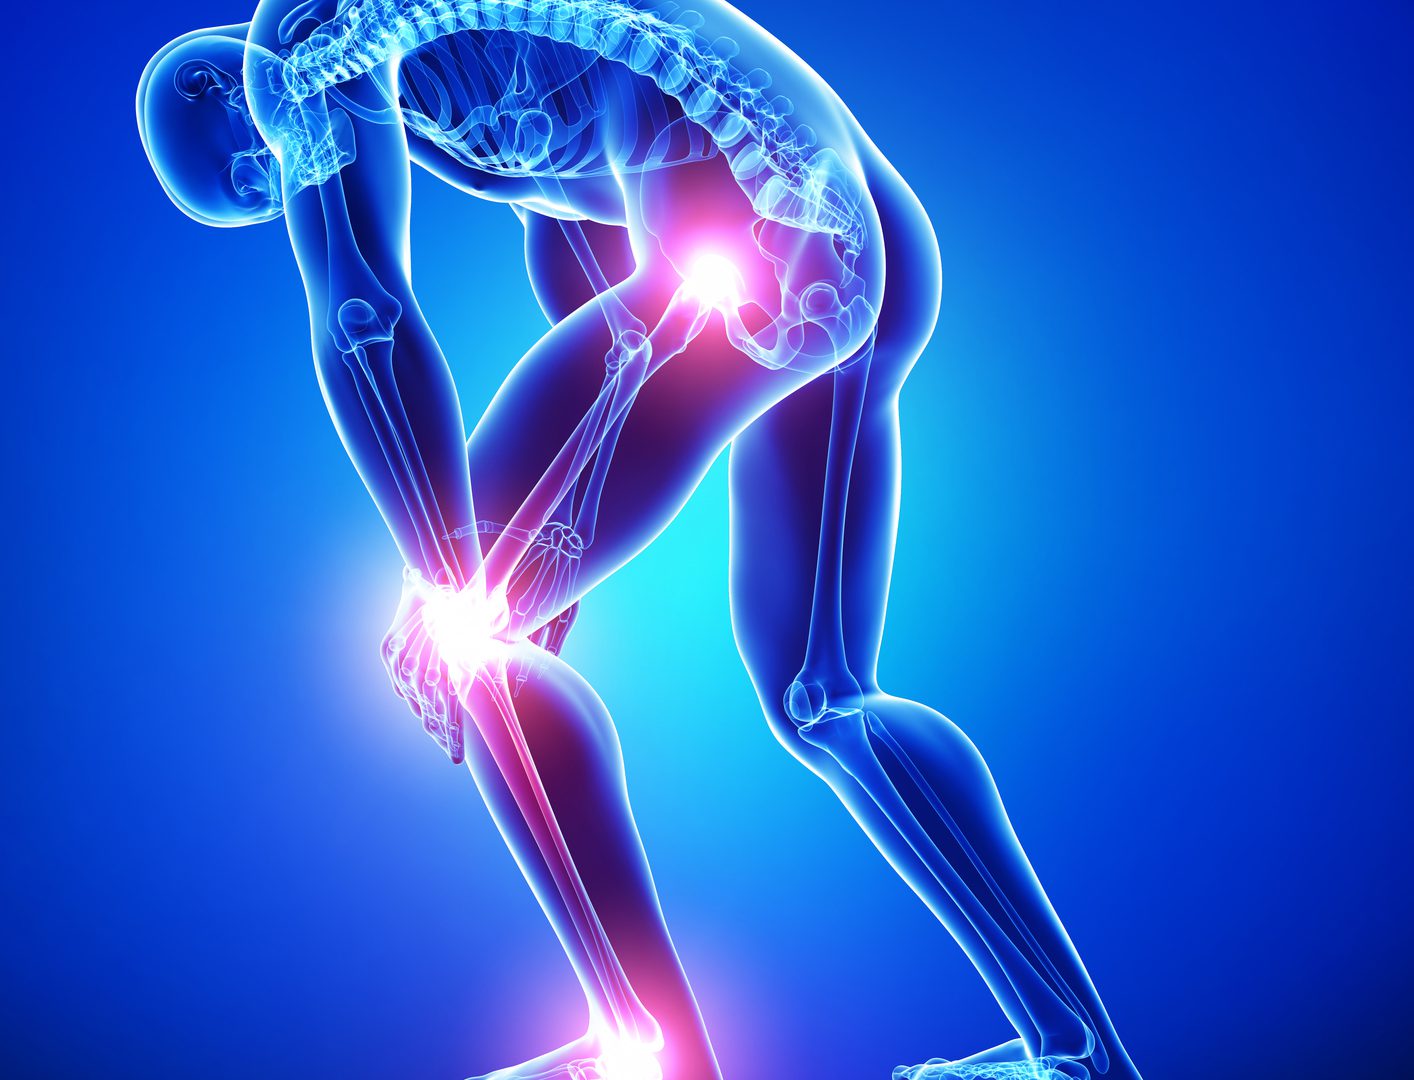

آرتروز: علت، علائم، و روشهای درمان

آرتروز یا استئوآرتریت (OA) یکی از شایعترین بیماریهای مفاصل است. این بیماری به دلیل فرسایش غضروفها و تخریب بافت مفصلی ایجاد میشود.

علائم آرتروز:

درد مفاصل

سفتی و محدودیت حرکت

تورم مفاصل